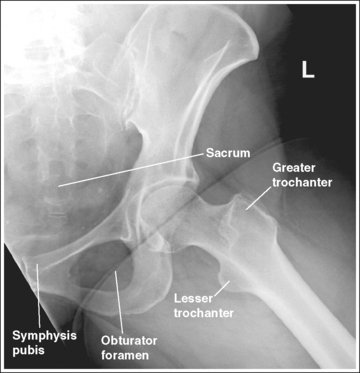

See Figures 7-21 and 7-22 and Box 7-5.

The pelvis demonstrates an AP projection. The ischial spines are aligned with the pelvic brim, the sacrum and coccyx are aligned with the symphysis pubis, and the ilia and obturator foramina are open and uniform in size and shape.

See Figure 7-26 and Box 7-6.

• Detecting pelvic rotation. A nonrotated AP oblique pelvis projection will demonstrate symmetrical ilia and obturator foramina. Rotation can be detected by evaluating the relationships of the ischial spines with the pelvic brim and of the sacrum and coccyx with the symphysis pubis. The ischial spines should be aligned with the pelvic brim and the sacrum and coccyx should align with the symphysis pubis on a nonrotated pelvis. If the pelvis is rotated into an LPO position, the left ilium is wider than the right, the left obturator foramen is narrower than the right, the left ischial spine is demonstrated without pelvic brim superimposition, and the sacrum and coccyx are not aligned with the symphysis pubis but are rotated toward the right hip (see Image 19). If the patient is rotated into an RPO position, the opposite is true. The right ilium is wider than the left, the right obturator foramen is narrower than the left, the right ischial spine is demonstrated without pelvic brim superimposition, and the sacrum and coccyx are rotated toward the left hip.

IMAGE 19

The left obturator foramen is narrower than the right foramen, the left ischial spine is demonstrated without pelvic brim superimposition, and the sacrum and coccyx are rotated toward the right hip. The patient was rotated onto the left hip (LPO).

Rotate the patient toward the right hip until the ASISs are positioned at equal distances from the imaging table.